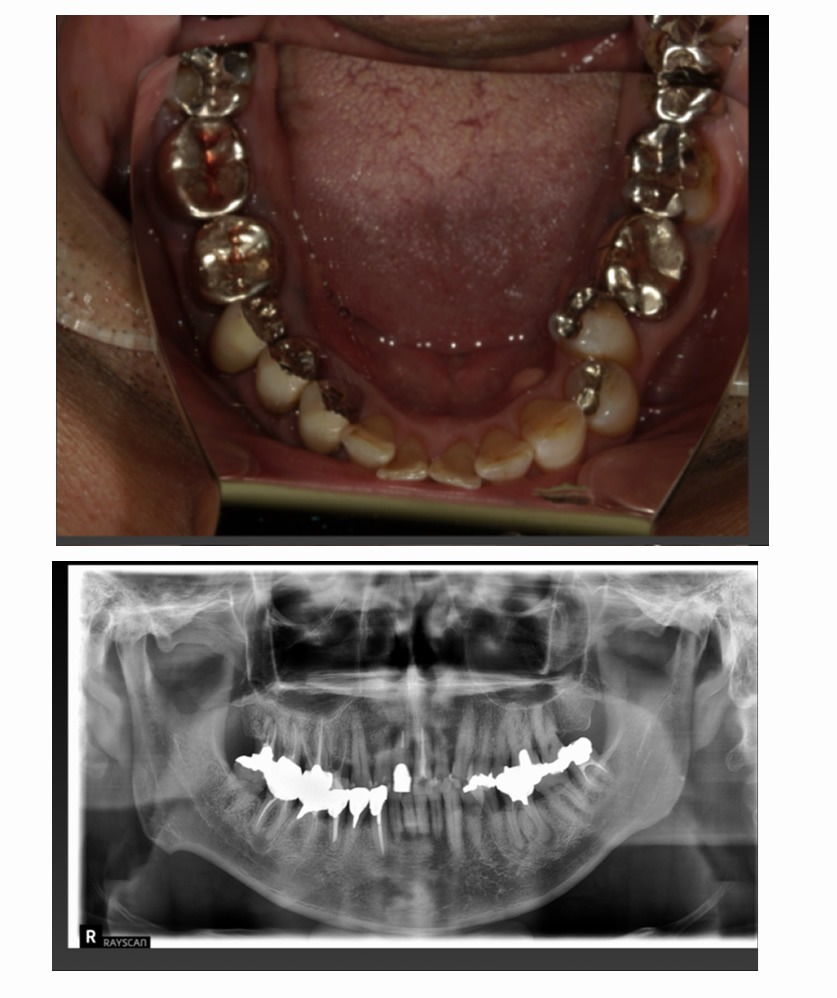

症例1

Before

After

年齢/性別 | 60代/女性 |

|---|---|

主訴 | 咬むと痛いのでインプラントにしたい |

治療内容 | 歯が割れていて咬むと痛いのでインプラント希望 |

治療期間 | 3ヶ月 |

費用 | 518,100円(税込み) |

副作用/リスク | 術後に多少の痛みや腫れが出ることがある。歯肉退縮がおきると、歯と歯肉の間に隙間が生じることがあります。 |